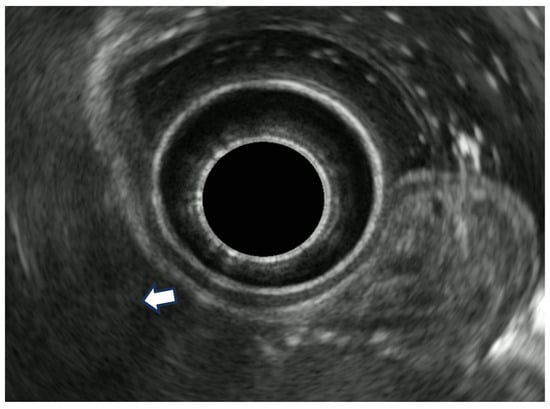

8.1. Rectal Superficial Cancer

8.2. Advanced Rectal Cancer

- Puli, S.R.; Bechtold, M.L.; Reddy, J.B.; Choudhary, A.; Antillon, M.R.; Brugge, W.R. How good is endoscopic ultrasound in differentiating various T stages of rectal cancer? Meta-analysis and systematic review. Ann. Surg. Oncol. 2009, 16, 254–265. [Google Scholar] [CrossRef] [PubMed]

- Marusch, F.; Ptok, H.; Sahm, M.; Schmidt, U.; Ridwelski, K.; Gastinger, I.; Lippert, H. Endorectal ultrasound in rectal carcinoma—Do the literature results really correspond to the realities of routine clinical care? Endoscopy 2011, 43, 425–431. [Google Scholar] [CrossRef]